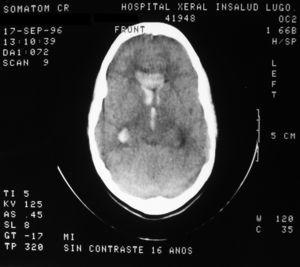

Una analítica, que incluía hemograma, estudio de coagulación y perfil bioquímico no mostró alteraciones. El electrocardiograma estaba en ritmo sinusal. La radiografía de tórax no evidenció alteraciones agudas. Se realizó TC cerebral (fig. 1) que mostró la presencia de sangre en el sistema ventricular sin sangre intraparenquimatosa. La niña fue ingresada con analgesia y sueroterapia, presentando una buena evolución clínica.

Figura 1.TC cerebral realizada en el momento del ingreso en la que se observa la presencia de sangre en el interior del sistema ventricular.